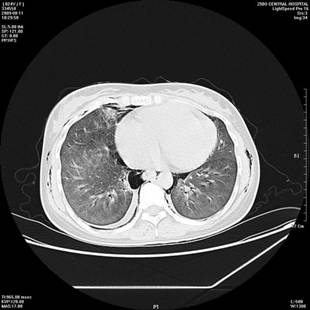

百草枯致肺纤维化CT图

而百草枯杀人的机理也与之类似,当人们服下百草枯后,百草枯可以从消化道迅速进入血液,进而被运输到身体各处,其中就包括我们的肺。肺因为存在胺类物质的转运系统,而PQ的结构与二胺、多胺、二胺二硫胱胺的结构类似,肺泡无法有效地识别它们,所以PQ会被肺泡大量的摄入。进入肺里的PQ与进入叶绿体一样,会生成很多自由基,然后与氧分子反应生成超氧自由基,再经超氧化物歧化酶歧化形成过氧化氢,进一步形成毒性更高的羟自由基,直接损害细胞结构。此外,PQ还可以抑制肺内脂肪酸的合成,大量消耗掉肺里一种叫做还原型辅酶Ⅱ(NADPH)的物质,许多依赖NADPH参与的反应都无法进行,最终导致肺纤维化,功能衰竭,患者死亡。